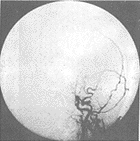

3.腦血管造影有一定的診斷價值71%以上的患者有典型的血管多灶性損害的表現,血管粗細不均,可呈節段性的狹窄或擴張血管阻塞及血管排空延遲等似“臘腸”樣改變,提示腦部血管炎的存在但不能明確是本病的血管炎其他的腦部繼發性血管炎也可有類似的表現有些可因受累的血管太小,腦血管造影可正常

除中樞神經系統症狀外可有發熱、體重下降等全身表現。腦脊液檢查可有細胞數及蛋白的升高,寡克隆區帶陽性。腦活檢可見肉芽腫樣血管炎和/或壞死性血管炎的表現。血管造影可見大腦中小動脈節段性狹窄、擴張及串珠樣改變。1988年Calabrese和Mallek提出了PACNS的診斷標準:①病史和臨床檢查發現原因不明的後天獲得性神經系統損害。②腦血管造影或腦活檢發現有典型血管炎表現。③除外系統性血管炎及其他能引起繼發性中樞神經系統血管炎(血管異常及組織學改變)的各種情況。本例基本皆符合此三條標準。